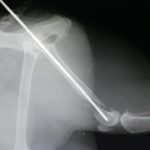

'זילולה' נעלמה ליותר משבוע וחזרה כשהיא לא דורכת על רגלה האחורית. בבדיקה וצילום במרפאה התגלה ש'זילולה' כנראה נדרסה ושברה שבר נוראי את רגלה. היא כנראה שברה את רגלה ביום שנעלמה, מאחר והשבר כבר לא היה "טרי", מה שסיבך מאוד את הטיפול בה. ואם לא די בכך, התקציב הטיפולי של 'זילולה' היה מוגבל ולא איפשר תיקון אורטופדי מתקדם.

כדי להציל את הרגל שלה, ביצענו ניתוח אורטופדי הרואי ומורכב, בו הצלחנו להחזיר את העצמות למנח כמעט אנטומי. וזאת כנגד כל הסיכויים כי השבר כבר התחיל בתהליך איחוי.